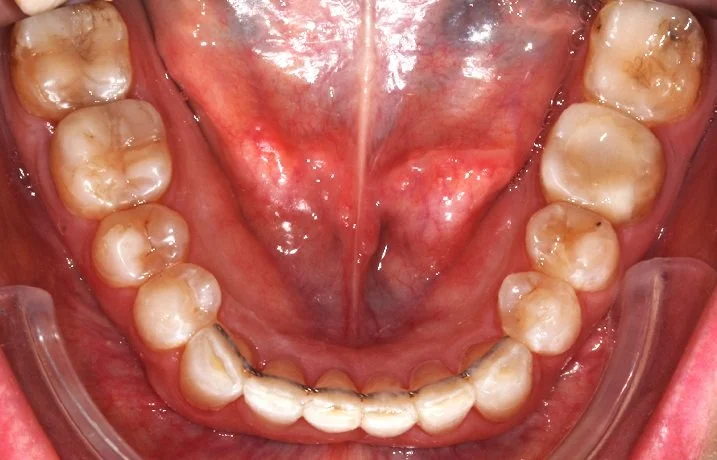

AFFOLLAMENTO INFERIORE

BEFORE

Caso di affollamento e disallineamento dei denti dell’arcata inferiore. Con una serie di allineatori trasparenti, si è ottenuto un ottimo allineamento dentale.